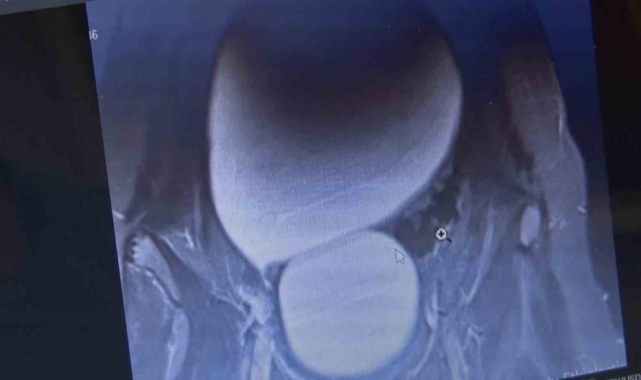

Sivas'ta yaşayan 12 yaşındaki N.B. şiddetli karın ağrıları ve düzensiz adet kanamaları şikayetiyle hastaneye başvurdu. Yapılan detaylı tetkikler sonucunda genç kızın karın bölgesinde yaklaşık 25 santimetre çapında adeta kavun büyüklüğünde bir kist olduğu tespit edildi. Medicana Sivas Hastanesi'nde Çocuk Cerrahisi Uzmanı Op. Dr. Mahmut Aluç tarafından gerçekleştirilen başarılı bir operasyonla, genç kızın sol yumurtalığında bulunan ve karaciğere kadar uzanan devasa kist içerisindeki 1.6 litre su boşaltılıp, başarıyla çıkarıldı. Sağlığına kavuşan genç kız taburcu edildi.

Çocuk Cerrahisi Uzmanı Op. Dr. Mahmut Aluç, kisttin içerisinden yaklaşık 1.6 litre sıvı boşaltıldığını söyleyerek, " Karın ağrısı, düzensiz adet şikayetiyle bize geldi. Dışarıda yapan tetkiklerde ve bizde yapılan tetkiklerinde karın içerisinde yaklaşık yirmi beş santimetrelik çapında bir kitli kitle tespit ettik. Burada da tetkiklerimize tekrar baktığımızda sol över kökenli bir kisttik yapı olduğunun farkına vardık. Gerekli incelemeleri yaptıktan sonra ve ailenin onayını aldıktan sonra hastayı operasyona aldık. Karaciğere kadar uzanan bir kisttik yapımız vardı. Onun içerisinde yaklaşık 1.6 litre sıvı boşalttık. Over dokusunu, yumurtalık dokusunu koruyarak kisti tamamen eksize ettik. Hastamızı şifayla taburcu ettik. Patoloji sonucumuz da iyi huylu olarak geldi" dedi.